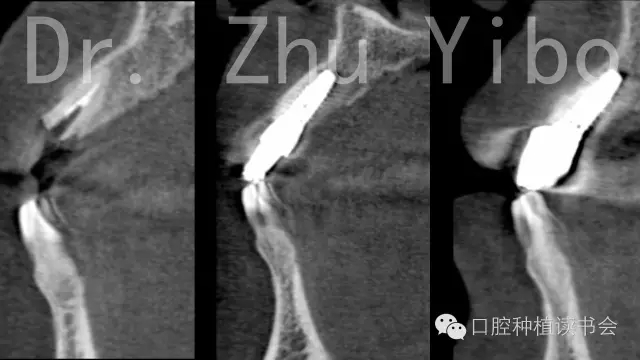

臨床檢查見:11殘根,松(-),齦(-),斷面齲壞,平齊牙齦齦,牙齦菲薄。21外翻(圖1)。術(shù)前根尖片及CBCT示:11根尖區(qū)低密度影,牙根腭側(cè)有橫向裂紋,唇側(cè)骨板薄,牙槽突與牙根長軸基本一致,符合一型分類(圖12、13)患者因時(shí)間、費(fèi)用問題,拒絕正畸治療,強(qiáng)烈要求即刻種植、即刻修復(fù)。

術(shù)前術(shù)后CBCT對(duì)比測量示:唇側(cè)牙槽骨穩(wěn)定(圖13)。術(shù)前術(shù)后石膏模型掃描,數(shù)字軟件重合對(duì)比測量:唇側(cè)牙齦組織穩(wěn)定(圖14)。